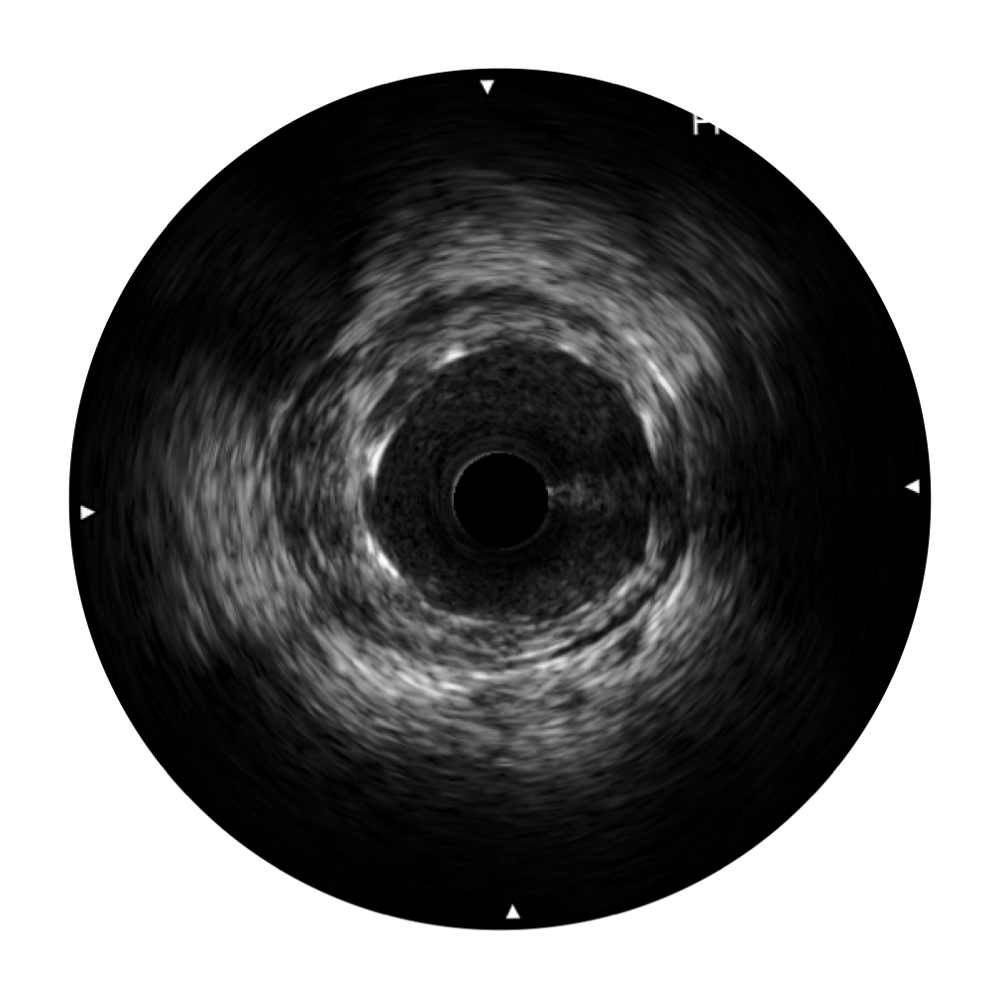

• 传统IVUS图像

对比传统IVUS导管成像,亚星官网宽频IVUS图像的近场支架梁显影更细腻,远场中膜外血管仍清晰可辨,兼顾远中近,兼顾分辨力与穿透深度